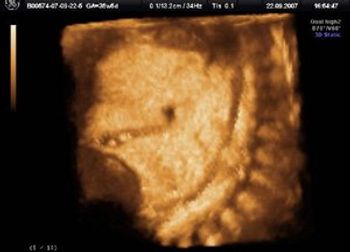

Diagnostics in the OB/GYN Setting